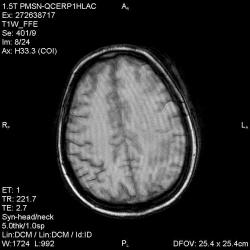

Из анамнеза - Женщина 45 лет. За год похудела на 15 кг (со слов матери), в последние месяцы случались эпизоды потери сознания. Онкозаболеваний и прочая в анамнезе нет. Сознание спутанное, из особенностей в анализах только подъем амилазы крови.

К сожалению, не владею методом КТ, но учитывая наличие неравномерного уплотнения в мозговых структурах с элементами очаговых "вкраплений", единственное, что приходит на ум - это рассеяный склероз. Хотелось бы уточнить, что беспокоило пациентку в течение последнего года кроме потери веса и эпизодов потери сознания? Была ли какая-либо очаговая неврологическая симптоматика? Отмечались ли какие-либо расстройства в двигательной или чувствительной сфере и т.д.? С уважением Helenmar.

И это точно не РС, т.к. характер очагов другой, ни один из них не копит контраст, нет субтенториальных очагов (извиняюсь, я этого в сообщении не указал), нет клиники.

"Раскрою" карты. Мы подумали о синдроме MELAS (mitochondrial encephalomyopathy, lactic acidosis and stroke) - дословно, митохондриальная энцефаломиелопатия, лактоацидоз и инсульт. В качестве дифференциальной диагностики можно было бы предположить вирусный энцефалит, но опять-таки, расположение очагов смущает - только с одной стороны и в абсолютно различных структурах.

В данном случае мы видим импульную последовательность FLAIR - режим с подавлением сигнала от воды, поэтому ликвор гипоинтенсивен, а также (вторая серия) - изображения, взвешенные по T1 после введения контрастного препарата. На T1 жидкость (ликвор) также представляется гипоинтенсивной. Зато на этих сериях гиперинтенсивны сосуды, т.к. контрастное вещество циркулирует в кровяном русле.

Изменения носят сосудистый характер. Процесс достаточно острый, имеется объемное воздействие, борозды левой гемисферы компремированы. По поводу MELAS синдрома очень сомневаюсь, почему поражена только левая гемисфера? Надо делать МР-ангиографию, смотреть нет ли стеноза

MELAS синдром - дебютирует с детских лет, характерен целый комплекс неврологических проявлений, заболевание генетическое, поражение системное, хотя есть множество вариантов митохондриального поражения, все же сомнительно. Хотелось бы акцентировать внимание, что гиперинтенсивные очаги есть в мозолистом теле, поражены выражено перивентрикулярные отделы, U -пути, белое вещество, поэтому так категорично демиелинизацию не вычеркивала бы из дифряда ( хотя тоже нетипично односторонее поражение). Думаю, для объективных выводов все же мало общей информации о пациентке, были ли клинические эпизоды раньше, чем объяснить такую потерю веса (возможно есть проявление паранеопластического синдрома?). Ну и МРТ-контроль в динамике, ангиография.

Да, неоднозначный случай. Точно не РС и не ОНМК. Я бы написала асимметричную лейкоэнцефалопатию неясного генеза. Можно было бы думать о лимфоме (полифокальное поражение, да еще мозолистое тело вроде бы задействовано (эх, сагиттальчики бы)). Но! Учитывая отсутствие накопления КВ.... Ну и надо исключать интоксикацию, всяческие аутоиммунные процессы (в т.ч. и васкулиты), сахарный диабет, ну и естественно наследственную патологию обменных процессов. УУУх! Вот.......

Имхо ишемический онмк в бассейне сма. Особенно показательны 5-й и 6-й файлы, отграничение как раз на границе бассейнов средней и перикаллёзной. Плюс одностороннее поражение.